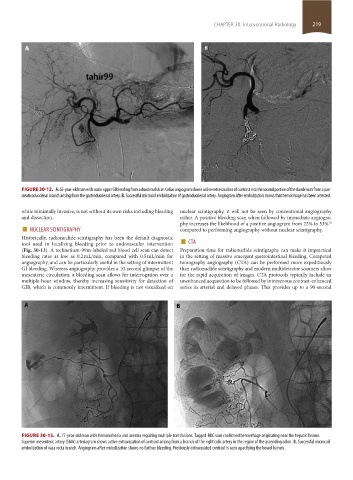

FIGURE 30-12. A. 63-year-old man with acute upper GI bleeding from a duodenal ulcer. Celiac angiogram shows active extravasation of contrast into the second portion of the duodenum from a pan-

creaticoduodenal branch arising from the gastroduodenal artery. B. Successful microcoil embolization of gastroduodenal artery. Angiogram after embolization shows that hemorrhage has been arrested.

FIGURE 30-13. A. 77-year-old man with hematochezia and anemia requiring multiple transfusions. Tagged-RBC scan confirmed hemorrhage originating near the hepatic flexure.

Superior mesenteric artery (SMA) arteriogram shows active extravasation of contrast arising from a branch of the right colic artery in the region of the ascending colon. B. Successful microcoil

embolization of vasa recta branch. Angiogram after embolization shows no further bleeding. Previously extravasated contrast is seen opacifying the bowel lumen.